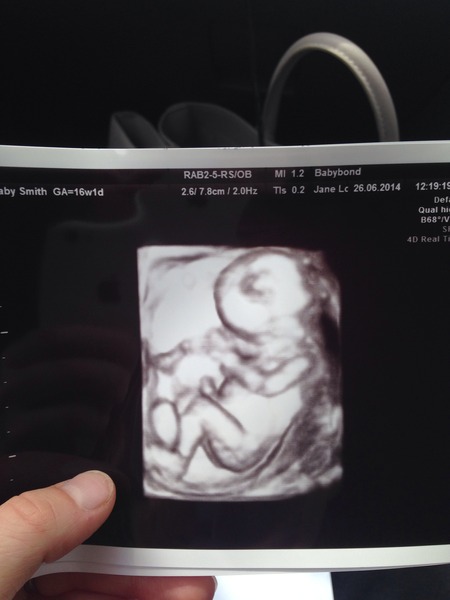

Really quick post from me.. Can anyone guess what we're having?! Haha!

Pregnant after MC due December 14

StrawbsAndCream · 26/06/2014 12:40

All perfect, it was so amazing.. I still can't believe it!!

A boy?

Yep!!! Grin

Oh wow fantastic news Strawbs yay for team blue!!

Heh, even I can tell it's a blue one! Congratulations Strawbs now I really really want to find out what we're having, dammit!

How exciting Strawbs and what a lovely pic. Little bit Envy that you got to see your baby again too. That's a proper baby that is!

Congratulations, Strawbs! What beautiful pictures! Smile